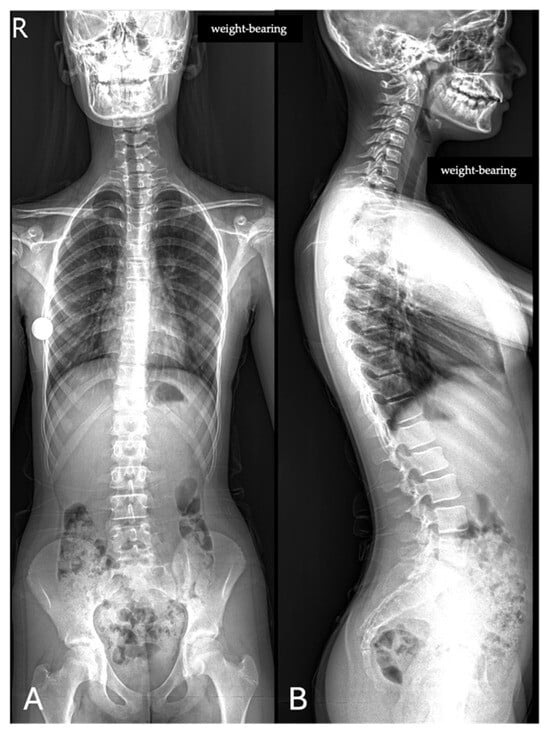

All images were acquired using the same digital radiography scanner (Bloomix 120 ED-R, Trade Art Manifacturing, Via della Pisana 1353, 00163 Rome, Italy) with patients in a standing weight-bearing position, in order to reproduce physiological load conditions on the spine. For each patient, both anteroposterior (AP) and lateral projections were obtained, covering the entire spine from the second cervical vertebra (C2) to the last sacral vertebral body (S5), including the pelvic bones and both femoral heads to allow evaluation of spinopelvic parameters. The dedicated scanner used in this study enables the acquisition of the entire spine in a single exposure, without the need for image stitching, thus reducing potential misalignment artifacts and ensuring greater measurement accuracy. Standardized positioning protocols were adopted to minimize patient rotation and to maintain consistent image quality across all examinations. All acquisitions were performed by experienced radiographers according to the department’s routine protocol for whole-spine evaluation. Exposure parameters, such as tube voltage and current, were adjusted based on patient size and age to optimize image quality while maintaining the radiation dose as low as reasonably achievable (ALARA principle) (Figure 1).

Figure 1. Full-spine radiographs were acquired in standing position using the same dedicated scanner (Bloomix 120 ED-R). (A) Anteroposterior (AP) view; (B) lateral view. For each patient, AP and lateral projections were obtained from the base of the skull to the last sacral segment, including the hip bones and femoral heads. The scanner enabled the acquisition of the entire spine in a single shot, without the need for image stitching.